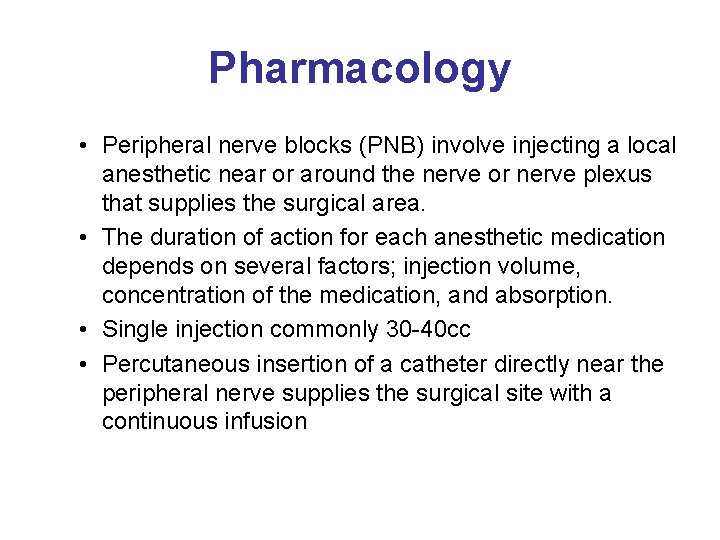

Pharmacology • Peripheral nerve blocks (PNB) involve injecting a local anesthetic near or around the nerve or nerve plexus that supplies the surgical area. • The duration of action for each anesthetic medication depends on several factors; injection volume, concentration of the medication, and absorption. • Single injection commonly 30 -40 cc • Percutaneous insertion of a catheter directly near the peripheral nerve supplies the surgical site with a continuous infusion